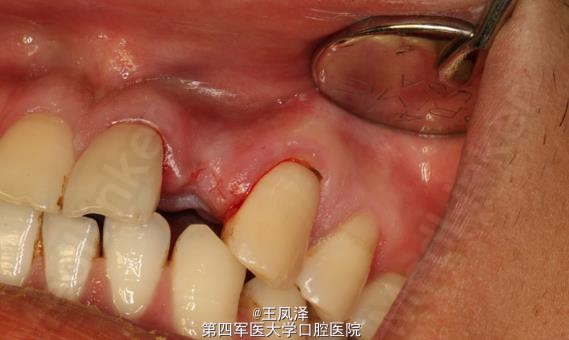

患者,刘某某、29岁,男性。主诉:上颌22烤瓷牙冠脱落,临床检查:22牙根唇舌向纵折,唇侧粘膜轻度红肿。

x线检查:22根尖区有阴影。诊断:22牙根纵折伴根尖周炎。

22牙根纵折伴根尖周炎。 治疗计划:1.拔除22. 2.三个月后延期种植22